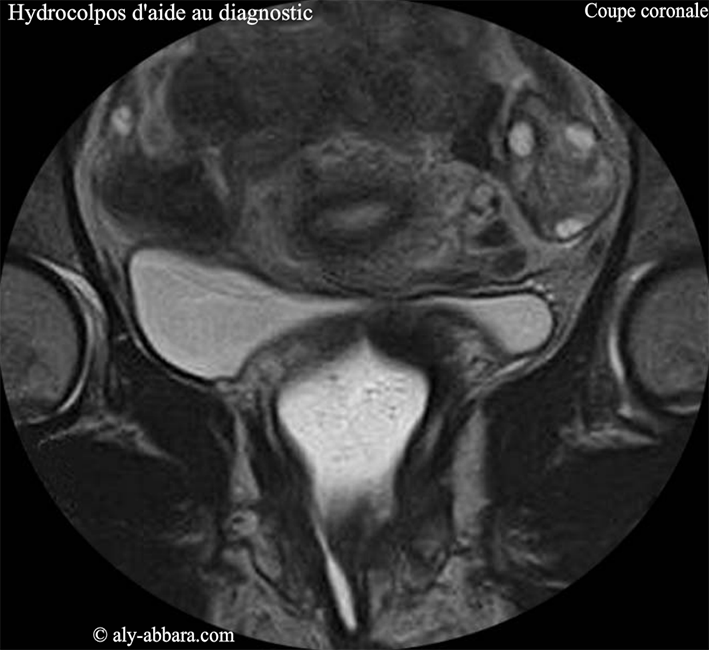

Coupe coronale (frontale) du pelvis par "IRM" centrée sur un hydrocolopos créé artificiellement en injectant dans la cavité vaginale, un gel permettant la mise en évidence le vagin afin de faciliter l'interprétation des coupes anatomiques du petit pelvis.